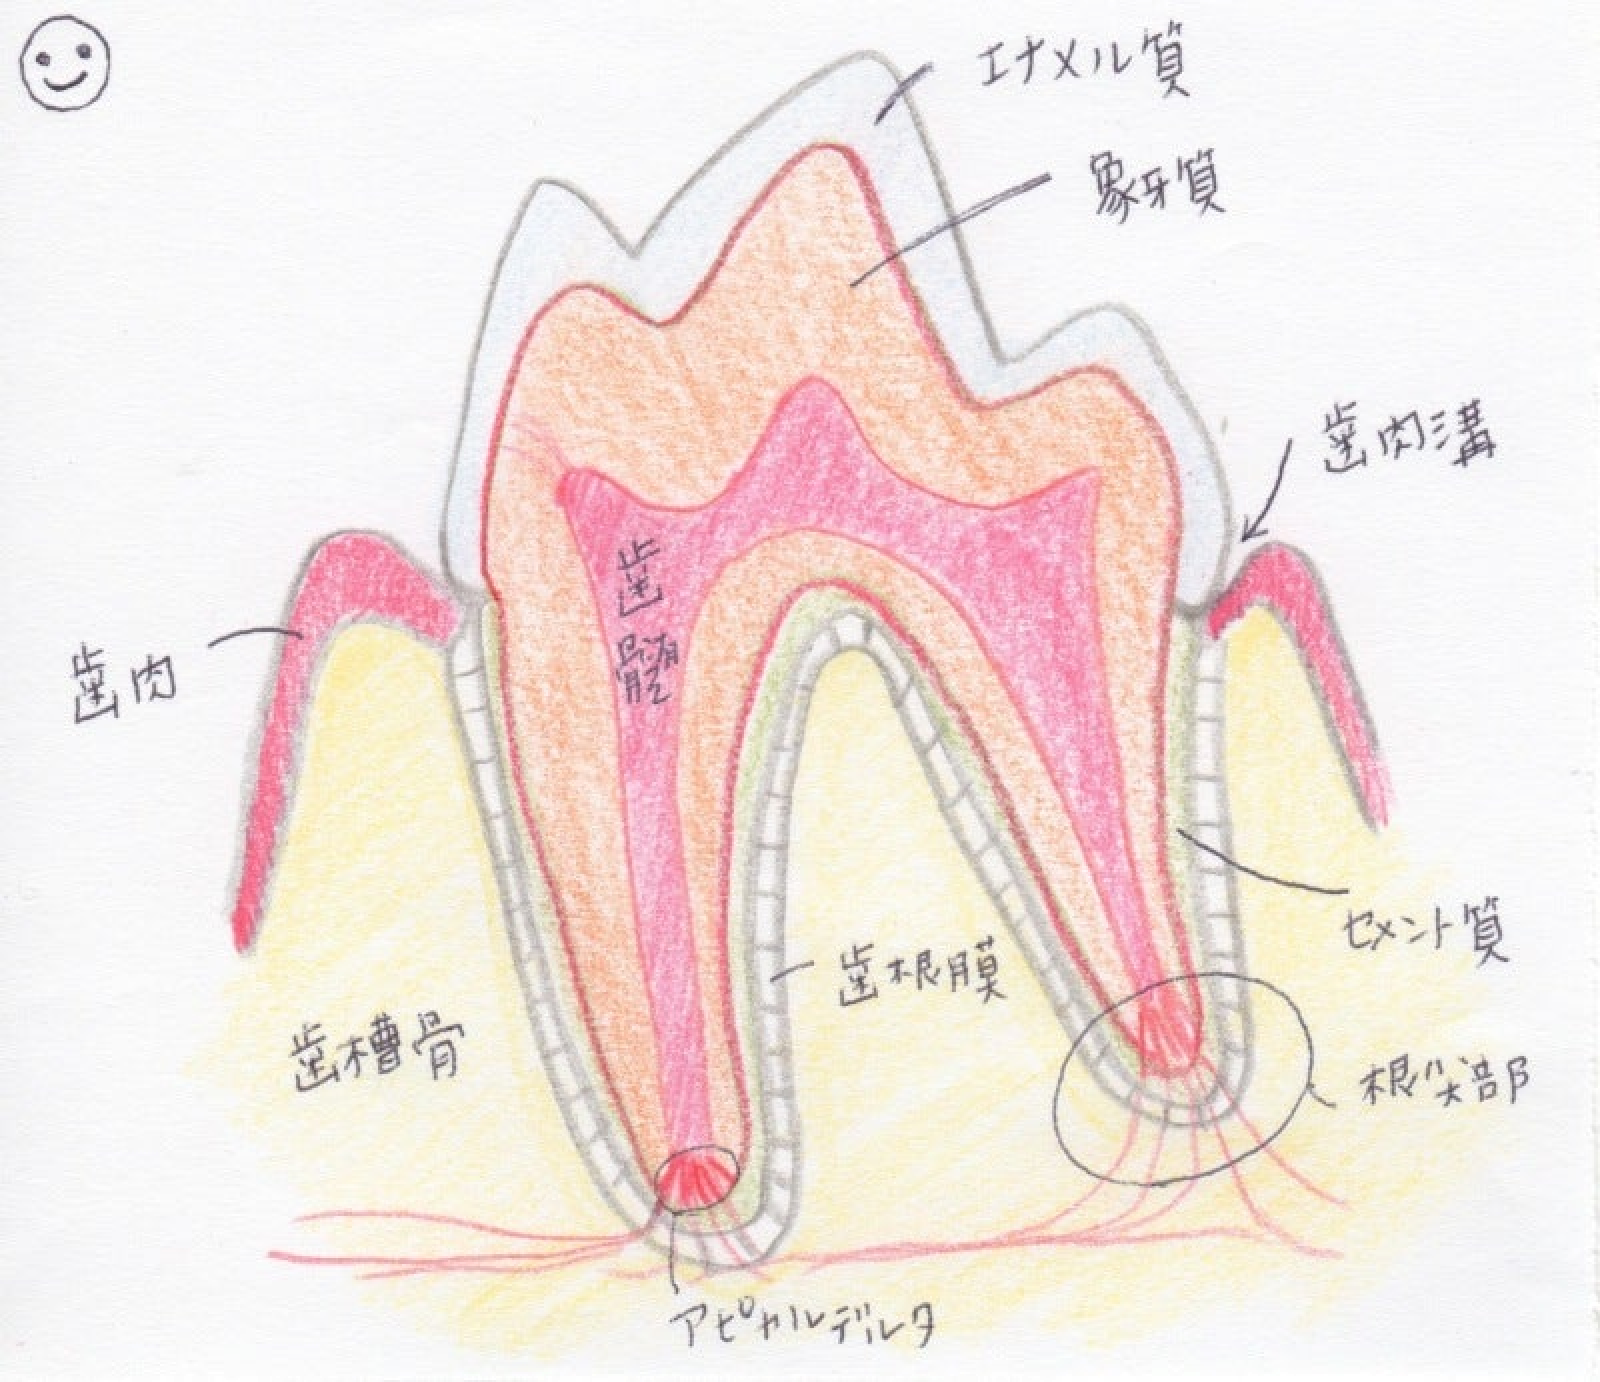

進行すると歯根周囲の骨が炎症により溶けてしまい、さらに膿が貯まることがあります。上顎の歯根に膿が貯まると、目の下や頬から貯まった膿が出てくる場合があります。

進行した歯周病の場合には、歯根や顎の骨が溶けてしまう事があります。これらの変化はレントゲン検査により確認することができます。(鎮静または麻酔が必要なことがあります)